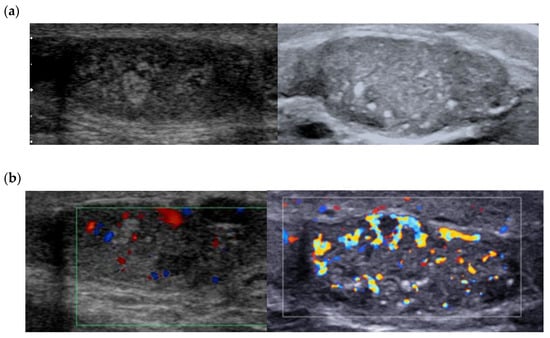

3.2. Color Doppler and Ultrasensitive Doppler